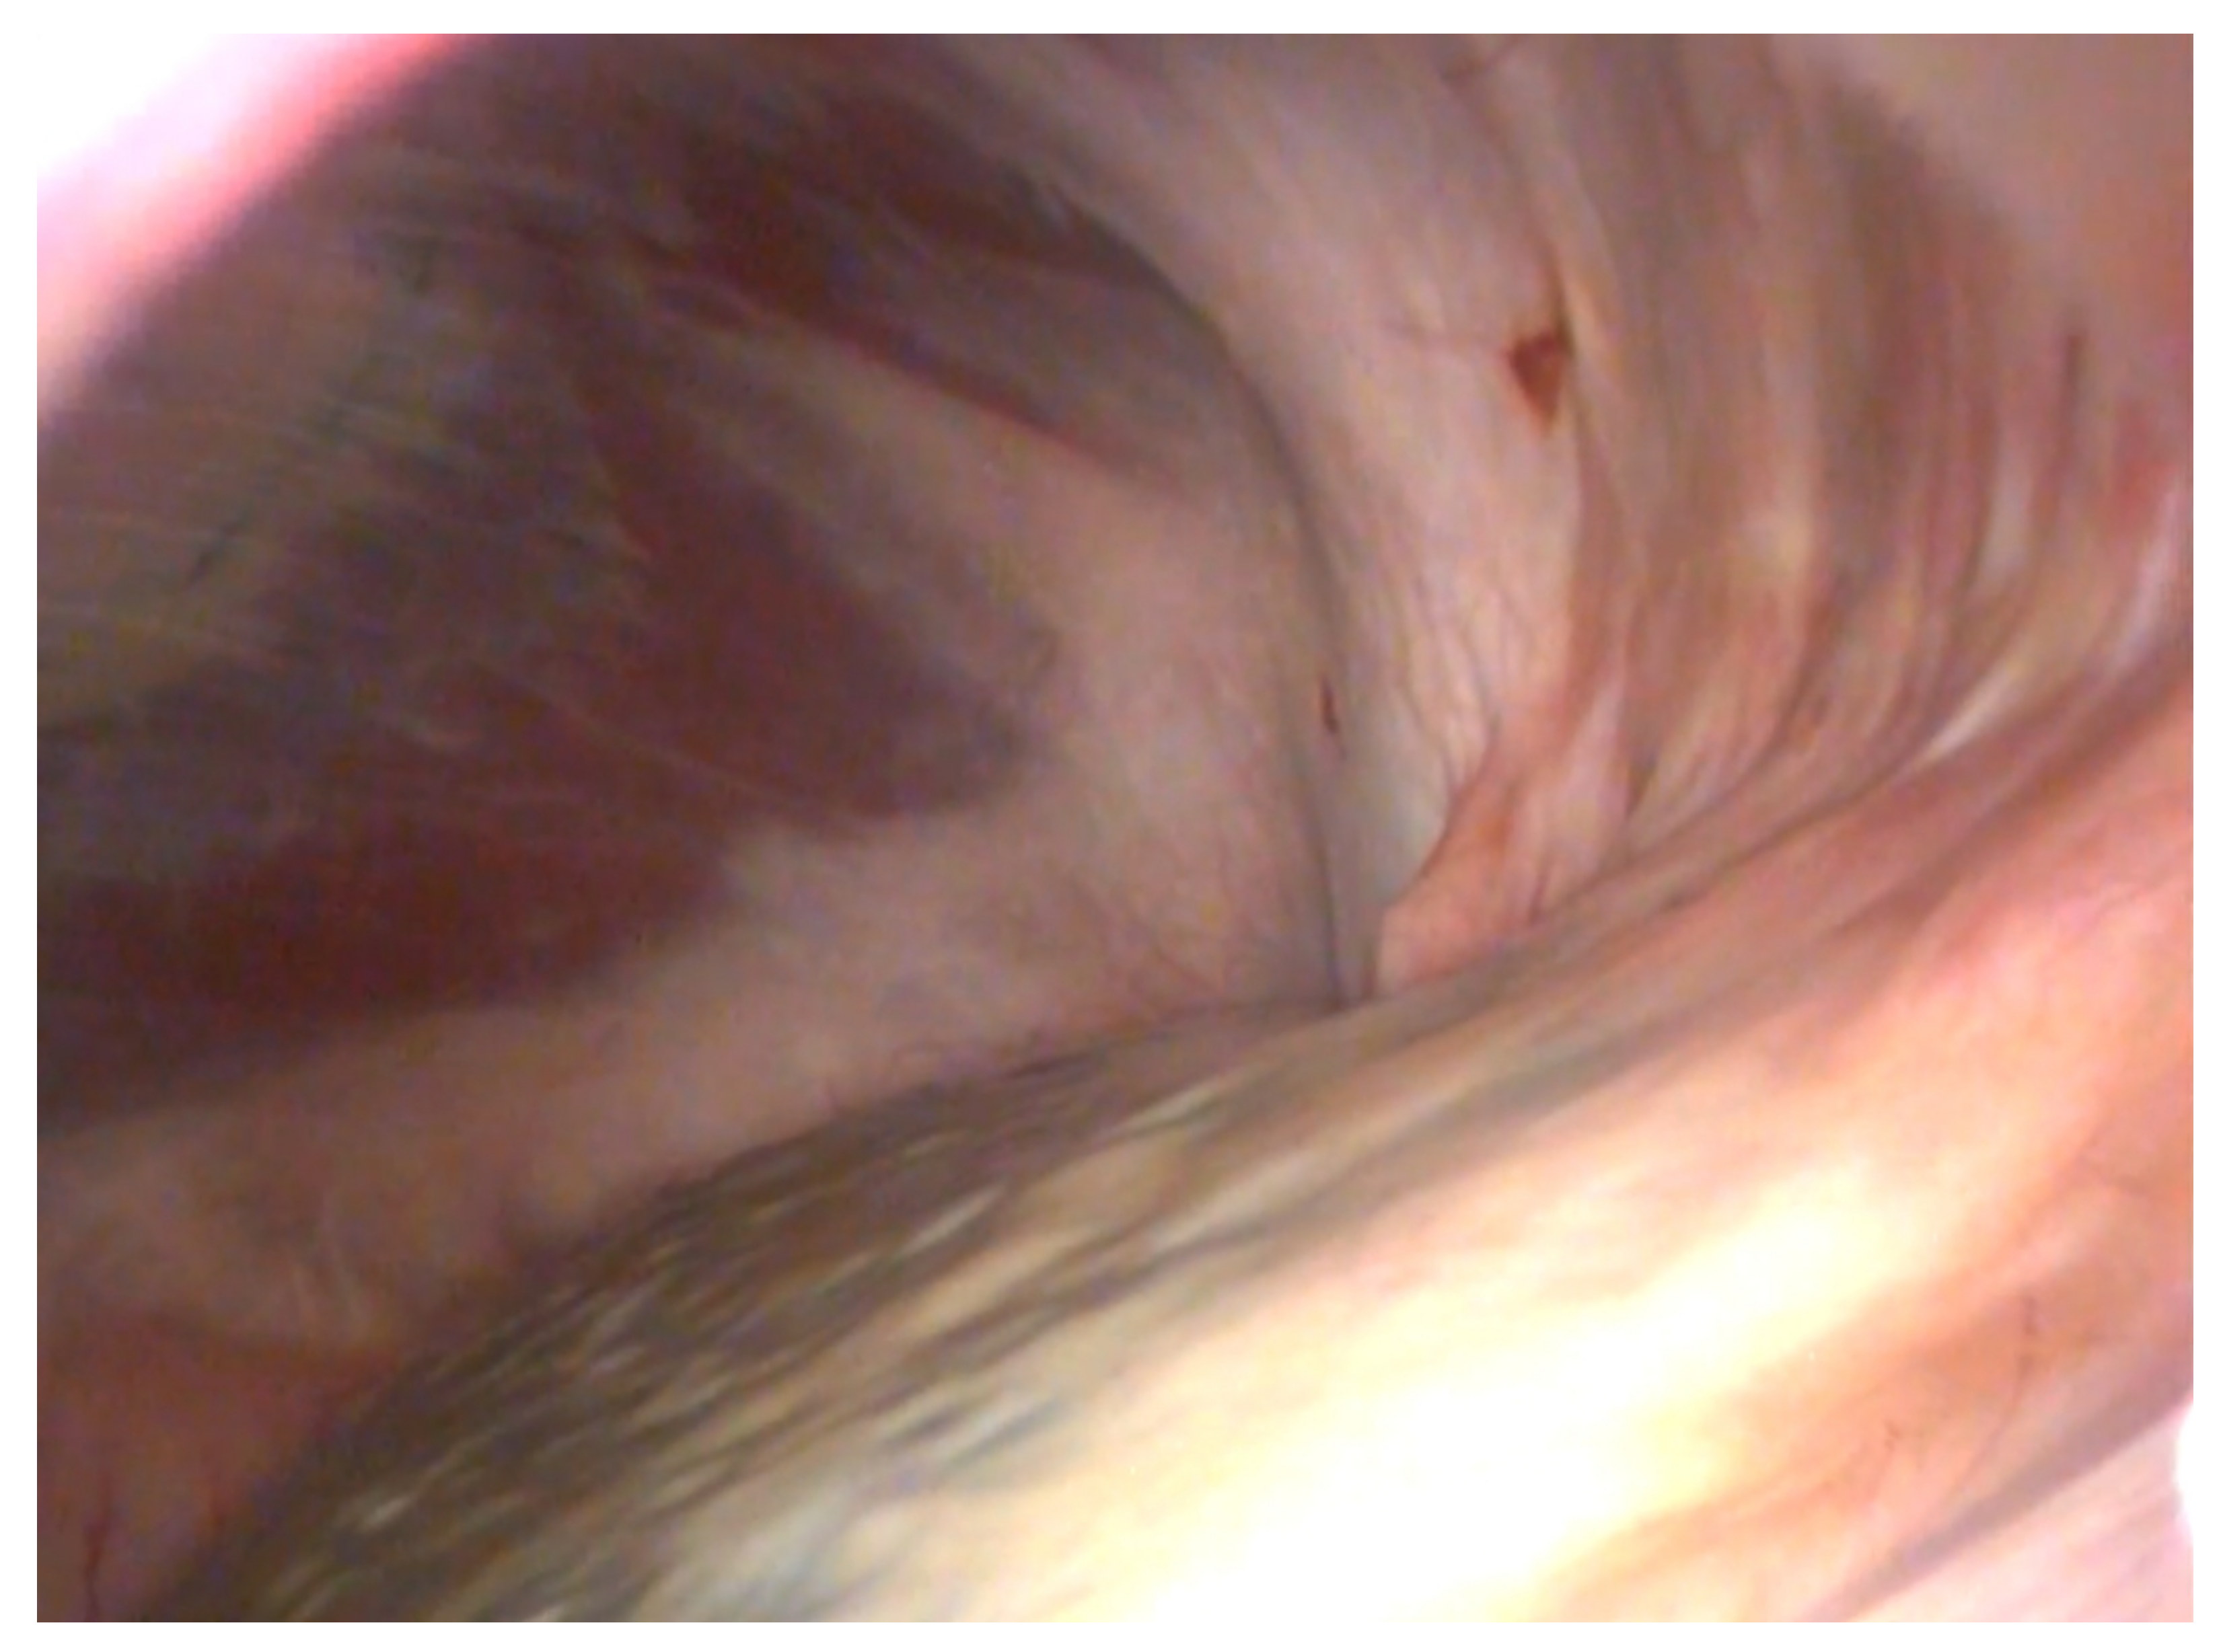

Four horses out of the 19 in group B underwent second-look laparoscopy (one for postoperative complications, the remaining three for other laparoscopic procedures) and in three horses neither adhesions nor other complications were observed and the NSS appeared fully ablated (Figure 3). One horse had recurrent colic after discharge. At control laparoscopy after 5 months, the NSS resulted in still not being ablated because of failure of the suture. The nephrosplenic space was further closed with barbed suture and at 6 months of follow-up the owner reported complete resolution of recurrent colic.

Figure 3. Second-look laparoscopy of an NSS space ablation with barbed suture.